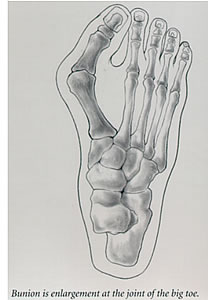

What is a Bunion?

A bunion is a painful enlargement at the joint of the big toe. The skin over the joint becomes swollen and is often quite tender. An important part of treatment is wearing shoes that conform to the shape of the foot and do not cause pressure areas. This often alleviates the pain. In severe cases, bunions can be disabling. Several types of surgery are available that may relieve pain and improve the appearance of the foot. Surgery is usually done to relieve pain and is not meant for cosmetic purposes.